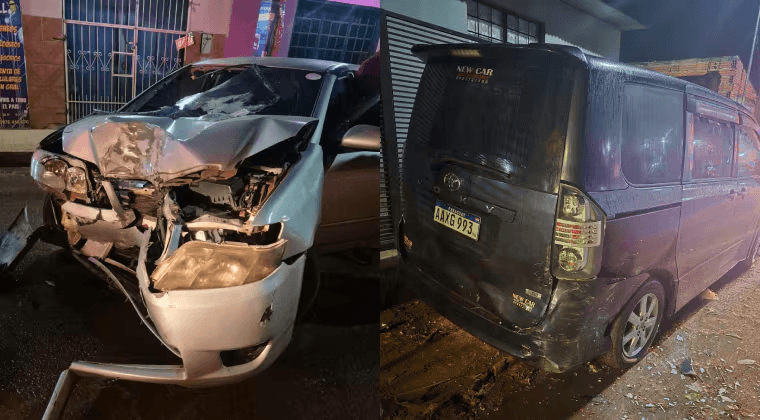

Niño tosió durante tres meses, tenía un resorte en el pulmón

Un pequeño de 5 años sufría de constante tos, desde hace tres meses, fue a consultar y se encontraron que tenía alojado un resorte en el pulmón. Médicos del Ineram realizaron una complicada cirugía para la extracción.

Un niño 5 años, oriundo de Guiará, llegó hasta el Hospital Regional de Villarrica, con cuadro de intensa tos, desde hace tres meses.

De acuerdo al reporte médico, del Dr. Carlos Morínigo, el niño fue sometido a una placa del tórax, se lo derivó inmediatamente hasta el Ineram y a tempranas horas de este jueves, fue sometido a una complicada cirugía para la extracción del metal del bronquio izquierdo.

Indicó, que el niño continúa en el Ineram, expresó que podría quedar con una leve secuela debido a la estrechez que quedará en el bronquio debido al daño que tuvo.